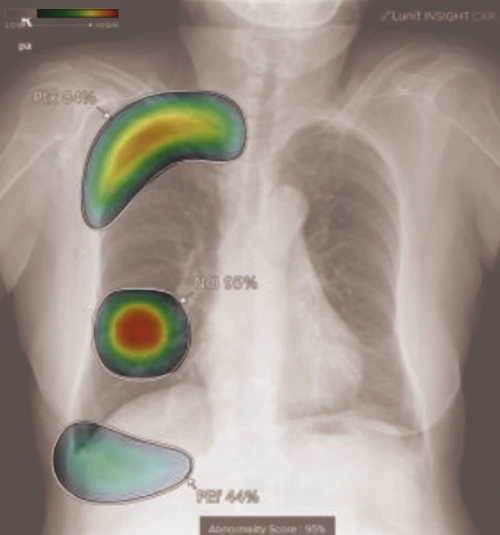

10개 폐 질환 검출

AI 흉부X선 3세대 진단시스템

서울대학교병원이 ㈜루닛과 함께 개발한 흉부 X선 인공지능 진단시스템 인사이트(Insight) 3세대 개발에 성공했다. 새로 개발한 3세대 진단시스템은 흉부 X선영상에서 폐암, 폐결절, 폐결핵, 폐렴, 기흉, 기복증, 종격동비대, 흉수, 폐섬유화, 심장비대 등 10가지 질환 소견을 찾아낸다. 사실상 대부분의 폐·흉곽 질환을 진단할 수 있다는 것이다. 진단시스템은 응급실을 내원한 환자들을 대상으로 한 실전 모의 판독 실험에서 더욱 빛을 발했다. 인공지능 시스템의 보조를 받은 경우, 영상판독 전문가 단독으로 진단할 때보다 진단 정확도가 상승했다. 특히, 기흉·기복증 등 초응급질환은 진단 정확도가 29.2%(7/24)에서 70.8%(17/24)까지 대폭 상승했다.